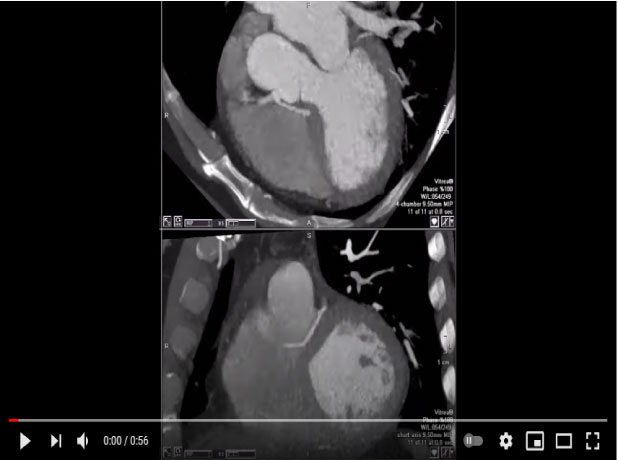

Trans-septal course of the anomalous LMCA from RCA

Mohamed Gibreel , FEBR (Fellowship of Egyptian Board of Radiology ) Cardiac imaging consultant at Aswan heart center -Magdi Yacoub Foundation , Egypt